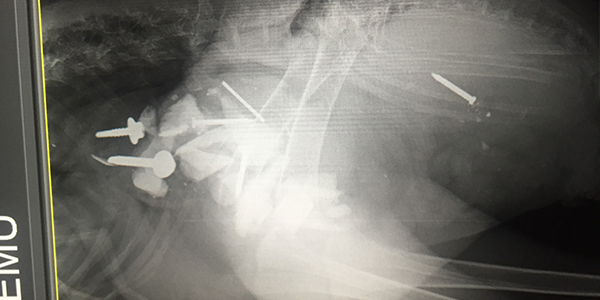

• X-Ray of Emu showing foreign bodies ingested

Emergency surgery was performed on the Emu at RSPCA Queensland's Wildlife Hospital at Wacol, to remove metal objects from his stomach.

RSPCA Veterinarian Dr. Meghan Burrows performed the 2.5 hour surgery on “Digger” and says he’s extremely lucky.

“The Emu had ingested the foreign objects some time ago and as a result they had caused significant damage to the bird,” she said.